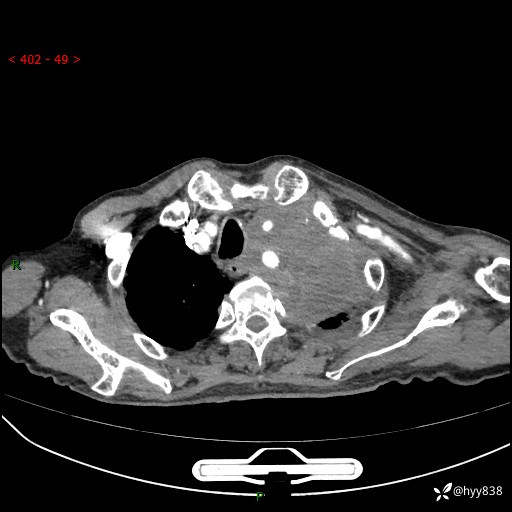

老年男性,气促5月,胸背痛2月。发现肺尖较大肿块,摧枯拉朽之势---结果公布~

现病史:患者于5月前饮酒后突发静息状态下气促不适,无胸闷、胸痛、发热、咳嗽、咳痰等不适,于当地第五人民医院及我院就诊,输液治疗后(具体不详)后气促稍缓解,遂出院后自行口服中草药治疗。近2月出现胸背痛,伴左上肢疼痛、乏力、感觉异常,稍有咳嗽、咳痰,咳黄痰、痰液粘稠,无咳血。为进一步诊治来我院。

胸部CT增强扫描(外院平扫)